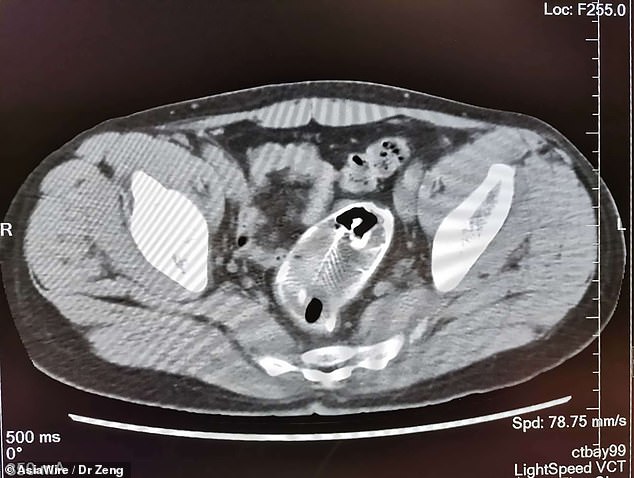

وحسبما ذكرته صحيفة "ديلي ميل" البريطانية، صُدم الأطباء عندما كشفت الفحوصات وجود سمكة كاملة في مستقيم الرجل من فصيلة البلطي الأزرق، وفي حين أن طول هذا النوع عادة ما يتراوح بين 30-40 سم، إلا أن هذه السمكة بلغ طولها 50 سم.

يكشف الفيديو عملية استخراج السمكة من مستقيم الرجل والذي زعم أنها علقت في المستقيم عندما جلس عليها عن طريق الخطأ، قبل لجوئه إلى المستشفى بعدما فشل في إخراجها بنفسه.

وأوضح الأطباء أن السمكة كانت كبيرة جدًا، ولجأوا إلى فتح بطن الرجل جراحيًا لاستخراجها من المستقيم، كما قالت ممرضة أن السمكة كانت عفنة للغاية.